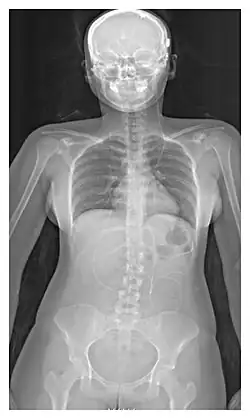

L'emplacement de la dérivation est déterminé par le neurochirurgien en fonction du type et de l'emplacement du blocage provoquant l'hydrocéphalie. Tous les ventricules cérébraux sont candidats à la dérivation. Le cathéter est le plus souvent placé dans l'abdomen, mais d'autres emplacements incluent le cœur et les poumons. les dérivations peuvent souvent porter le nom de la voie utilisée par le neurochirurgien. L'extrémité distale du cathéter peut être située dans à peu près n'importe quel tissu comportant suffisamment de cellules épithéliales pour absorber le LCR entrant. Ci-dessous quelques plans de routage courants pour les dérivations cérébrales :

| Dérivation ventriculo-péritonéal (Dérivation VP) | Cavité péritonéale |

| Dérivation ventriculo-auriculaire (Dérivation VA) | Oreillette droite du cœur |

| Dérivation ventriculo-pleural (Dérivation VPL) | Cavité pleurale |

| Dérivation lombaire-péritonéal (Dérivation LP) | Cavité péritonéale |